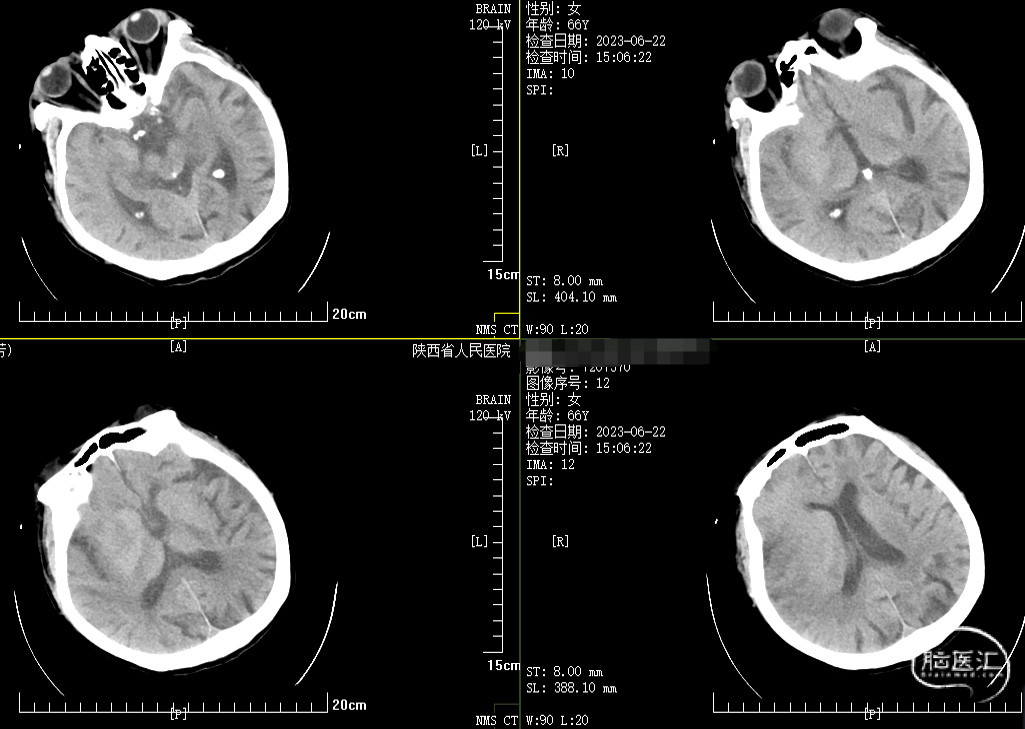

急诊CT

术前急诊MRA提示:右侧颈内动脉、大脑中动脉及右侧大脑前动脉局部管腔未见显示,考虑严重狭窄或闭塞。

颅脑DWI与Flair成像存在错配,颅脑CT的ASPECT评分小于6分,NIHSS评分25分。

66岁女患,急性起病,起病2小时,临床主要表现为意识障碍及左侧肢体瘫痪。神经系统查体:意识浅昏迷,双侧瞳孔等大等圆,直径3mm,对光反射迟钝,双眼向右侧凝视。左侧肢体坠落试验阳性,右侧肢体可见自主运动,四肢肌张力增高,左侧著。四肢腱反射对称(++),感觉及共济运动查体不合作。双侧巴氏征阳性。脑膜刺激征(-)。颅脑CT+MR支持:大面积脑梗死、右侧颈内动脉闭塞诊断,颅脑DWI与Flair成像存在错配,颅脑CT的ASPECT评分小于6分,NIHSS评分25分。